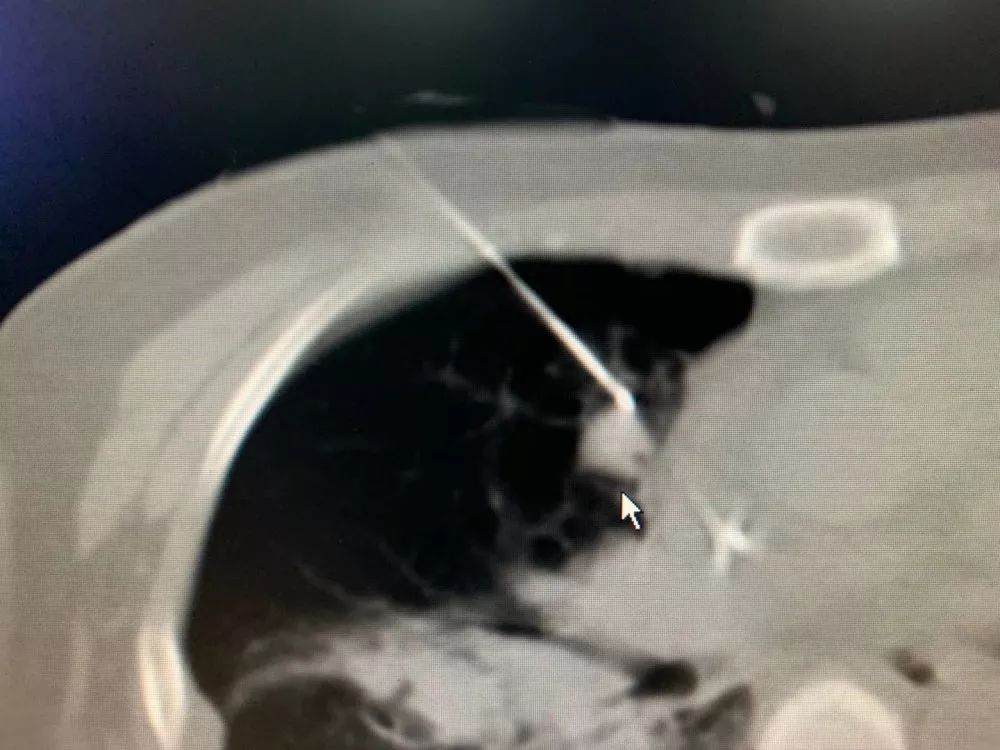

肺部肿瘤病灶

副院长牛立志教授为主刀医师,当手术开始,牛教授先用一根冷冻针像“钓鱼”一样把肿瘤“勾”住,然后慢慢从靠近心脏的危险地带中钓出这条“毒鱼”,把它放在安全的区域进行冷冻消融,尽可能避免对心脏造成损伤。因为心脏布满丰富的血管,肿瘤靠近心脏,一旦触碰到大静脉极易引起出血。这个看似简单的过程却十分考验一个医师的经验,既高度集中精神将肿瘤移出消融,也要时刻紧盯着心脏等重要器官是否正常运行。整个手术不允许有丝毫的偏差,耗时一个多小时才结束。